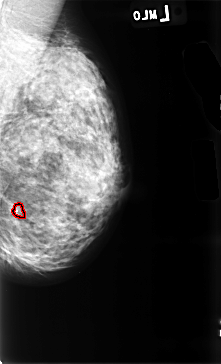

B_3455_1.LEFT_MLO

FILE: B_3455_1.RIGHT_MLO.OVERLAY

TOTAL_ABNORMALITIES 1

ABNORMALITY 1

LESION_TYPE CALCIFICATION TYPE PLEOMORPHIC DISTRIBUTION CLUSTERED

ASSESSMENT 4

SUBTLETY 4

PATHOLOGY BENIGN_WITHOUT_CALLBACK

TOTAL_OUTLINES 1

BOUNDARY